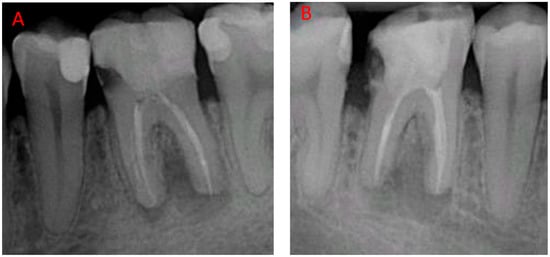

2.1. Surgical Protocol